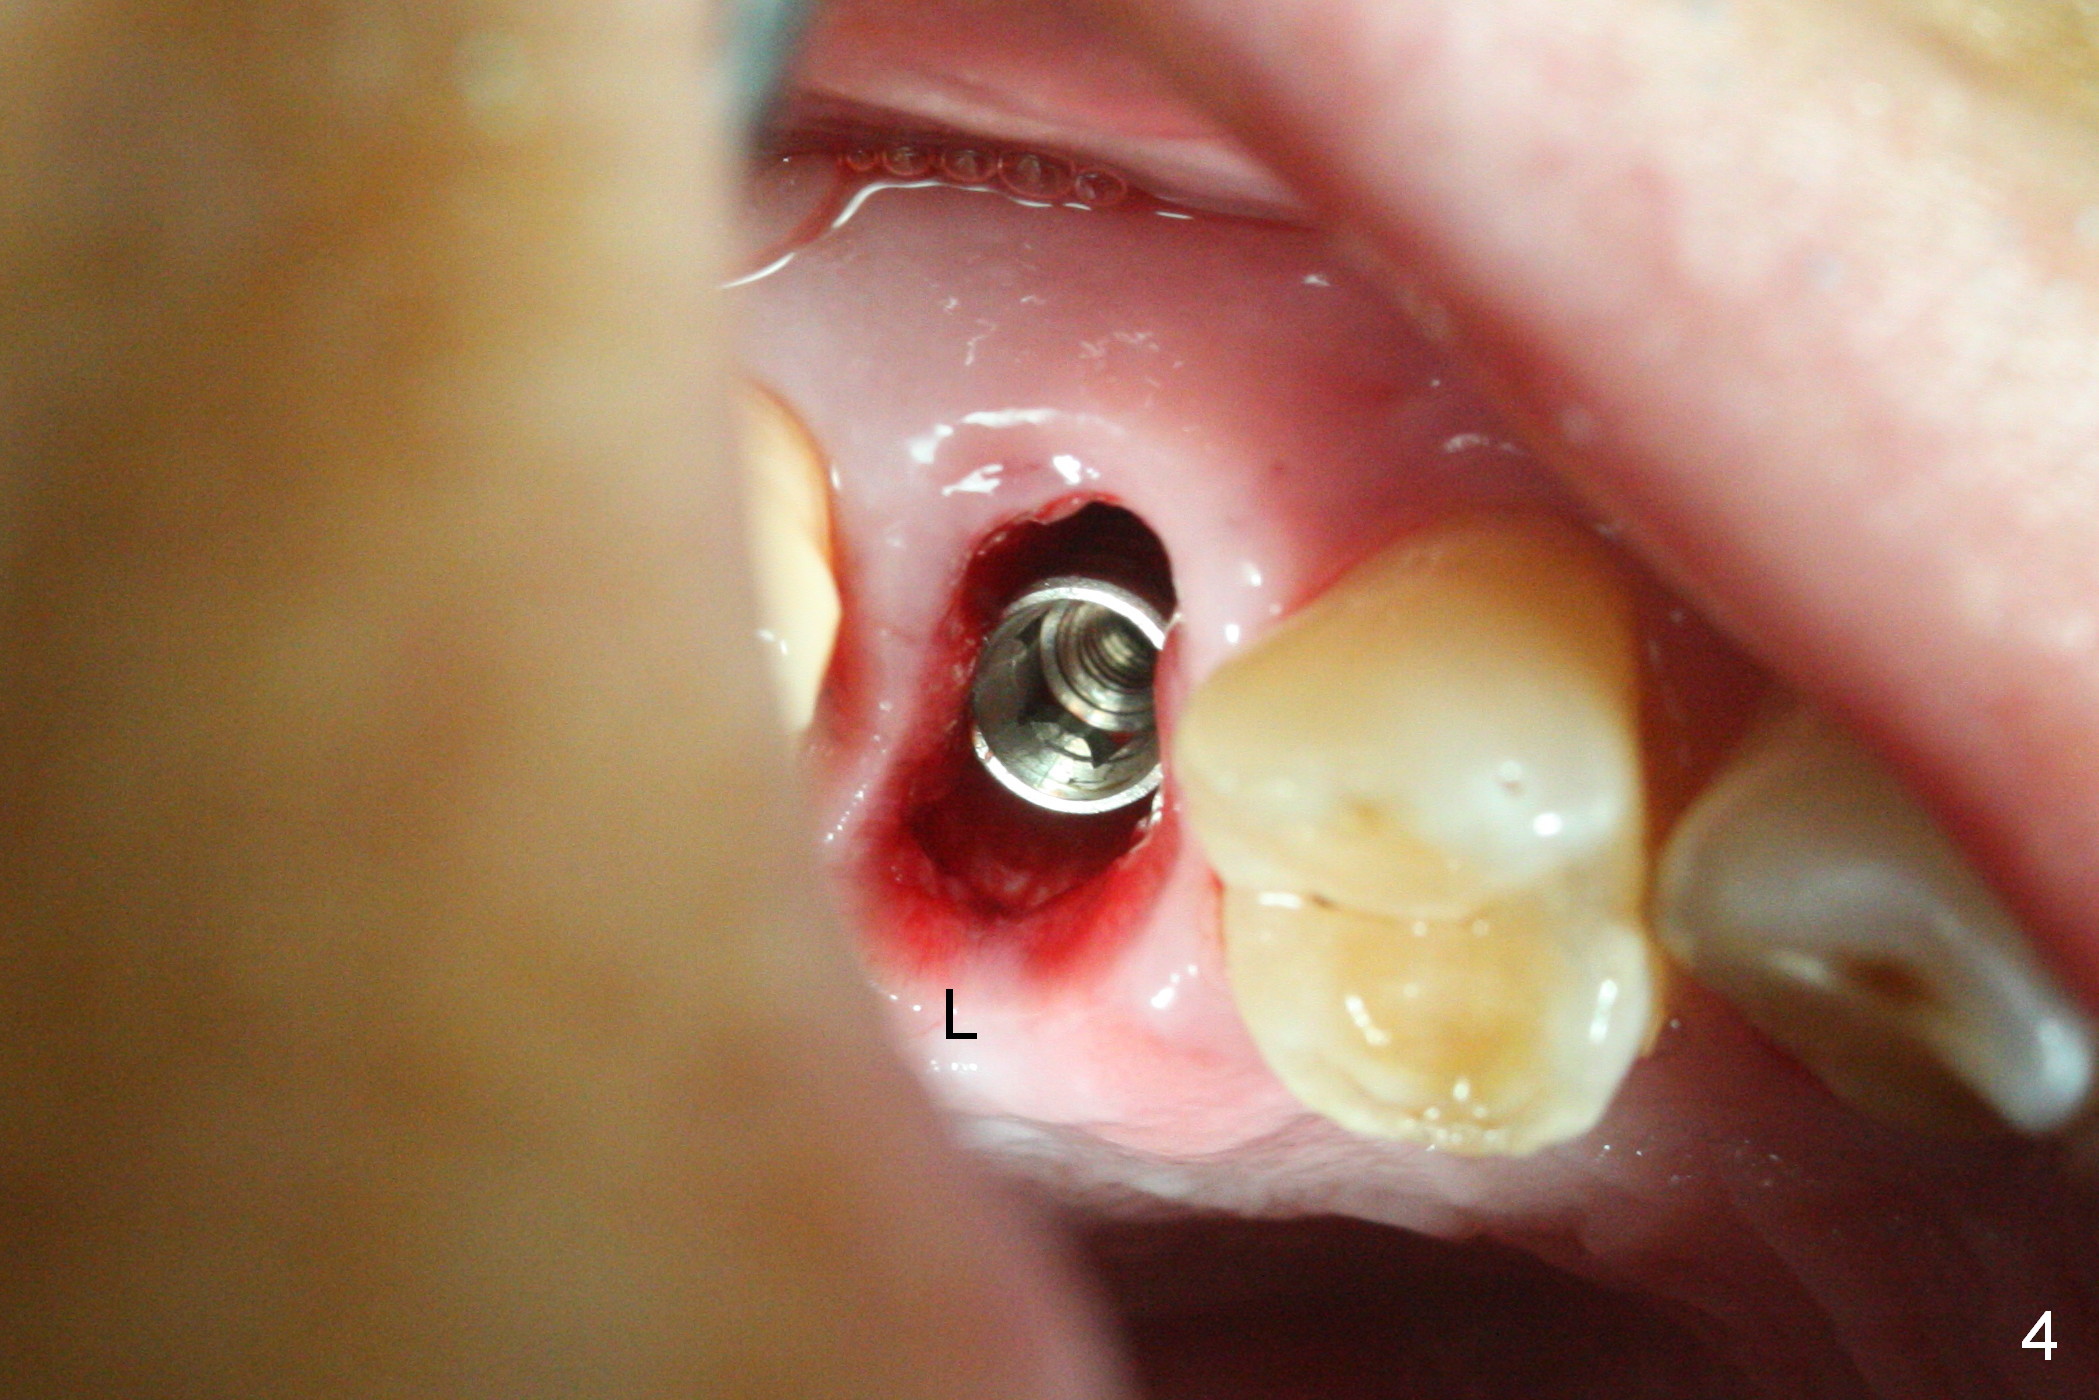

A 47-year-old man returns emergently with subgingival fracture of the lingual (L) cusp of the tooth #4 (Fig.1-3). After extraction (no bony defect) without drilling, a 4x11 mm dummy implant is placed as a tap drill with satisfactory stability (Fig.4,5). To get subcrestal placement, a shorter (4x9 mm) implant is inserted with insertion torque of < 35 Ncm. In retrospect, a larger implant (4.5 mm) would be better in term of primary stability. After allograft placement into the buccal and lingual gaps, a 4.5x4(4) mm abutment is placed for an immediate provisional. There is a peri-implant gap 7 months postop (Fig.7<, as compared to the implant at #2 (6 months postop)) . When the loose abutment is being retightened, the patient feels pain, although the gingiva appears healthy (Fig.8). A larger implant should have been used; the abutment should have been removed. The implant dislodges while the abutment is untightened 8 months postop. The osteotomy is found intact. A 4.5x11 mm dummy implant is placed 2 mm subgingival with 20 Ncm (Fig.9). When a 4.5x11 mm definitive implant is placed 3 mm subgingival (Fig.10,11), torque reaches 50 Ncm. A 5.5x3 mm healing abutment is placed. Three months postop, the implant is stable (Fig.12,13) and impression is taken.